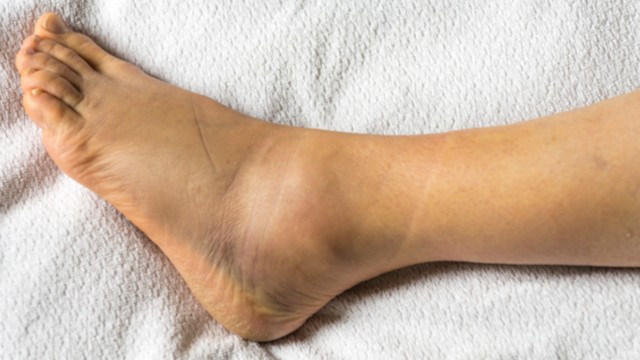

Rạn xương mắt cá chân bao lâu thì khỏi? Rạn xương mắt cá chân là một chấn thương phổ biến, thường gặp ở những người chơi thể thao, vận động viên hoặc người gặp tai nạn. Tình trạng này gây ra nhiều đau đớn, ảnh hưởng đến khả năng vận động và sinh hoạt của người bệnh.

Rạn xương mắt cá chân là một vấn đề y tế thường gặp khi xảy ra các tai nạn, bao gồm cả tai nạn giao thông và các tai nạn khác trong sinh hoạt hàng ngày. Xương cổ chân chịu áp lực lớn từ trọng lượng cơ thể và các hoạt động vận động, vì vậy khi bị tổn thương, nó có thể gây ra đau đớn, khó khăn trong việc di chuyển và ảnh hưởng đến chất lượng cuộc sống của người bệnh.